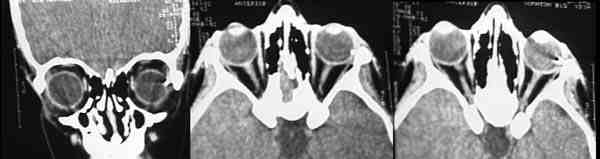

La utilización de Rayos X (figura 15) con proyecciones Caldwell, Waters, o las antero-posteriores pueden demostrarnos la presencia, pero no la localización, de un CEIO radiopaco y no detectará CEIO radiotransparentes, como la madera o el cristal. La ecografía nos ofrece una mejor localización del CEIO y es esencial para obtener información acerca de otros cambios estructurales como desprendimientos de retina o coroides. Al realizar esta exploración, han de tomarse precauciones para no comprimir el globo, sobretodo en los que presentan grandes heridas, y no producir prolapsos adicionales de su contenido. La ecografía con un estudio sistemático, con abordaje transversal y longitudinal puede determinar la localización del CEIO. La ultrasonografía biomicroscópica nos aporta algo más a la hora de diagnosticar cuerpos extraños ocultos o de polo anterior (123-125). La tomografía computerizada (TC) es el método diagnóstico de elección porque localiza y detecta CEIO radiopacos y radiotransparentes en 3 dimensiones. La TC tiene ciertas limitaciones y los CEIO metálicos crean artefactos significativos, que pueden dificultar la localización exacta. Esto puede ser un inconveniente a la hora de determinar si la localización de un CEIO es intrarretiniana o intraescleral. Asímismo la TC puede presentar problemas a la hora de identificar algunos CEIO de baja densidad, como la madera. Chacko, nos presenta en su artículo una interesante comparación entre la Tomografía Computerizada clásica (figura 16) y el TAC helicoidal (figura 17), demostrándose esta última más eficaz para la localización espacial de cuerpos extraños intraoculares o intraorbitarios (126).

63-16.jpg (11435 bytes)

Figura 16. Perdigón que pasa a través del ápex orbitario destrozando el nervio óptico.

63-17.jpg (11175 bytes)

Figura 17. La tomografía computerizada (TC) es el método diagnóstico de elección porque localiza y detecta CEIO radiopacos y radiotransparentes en 3 dimensiones.